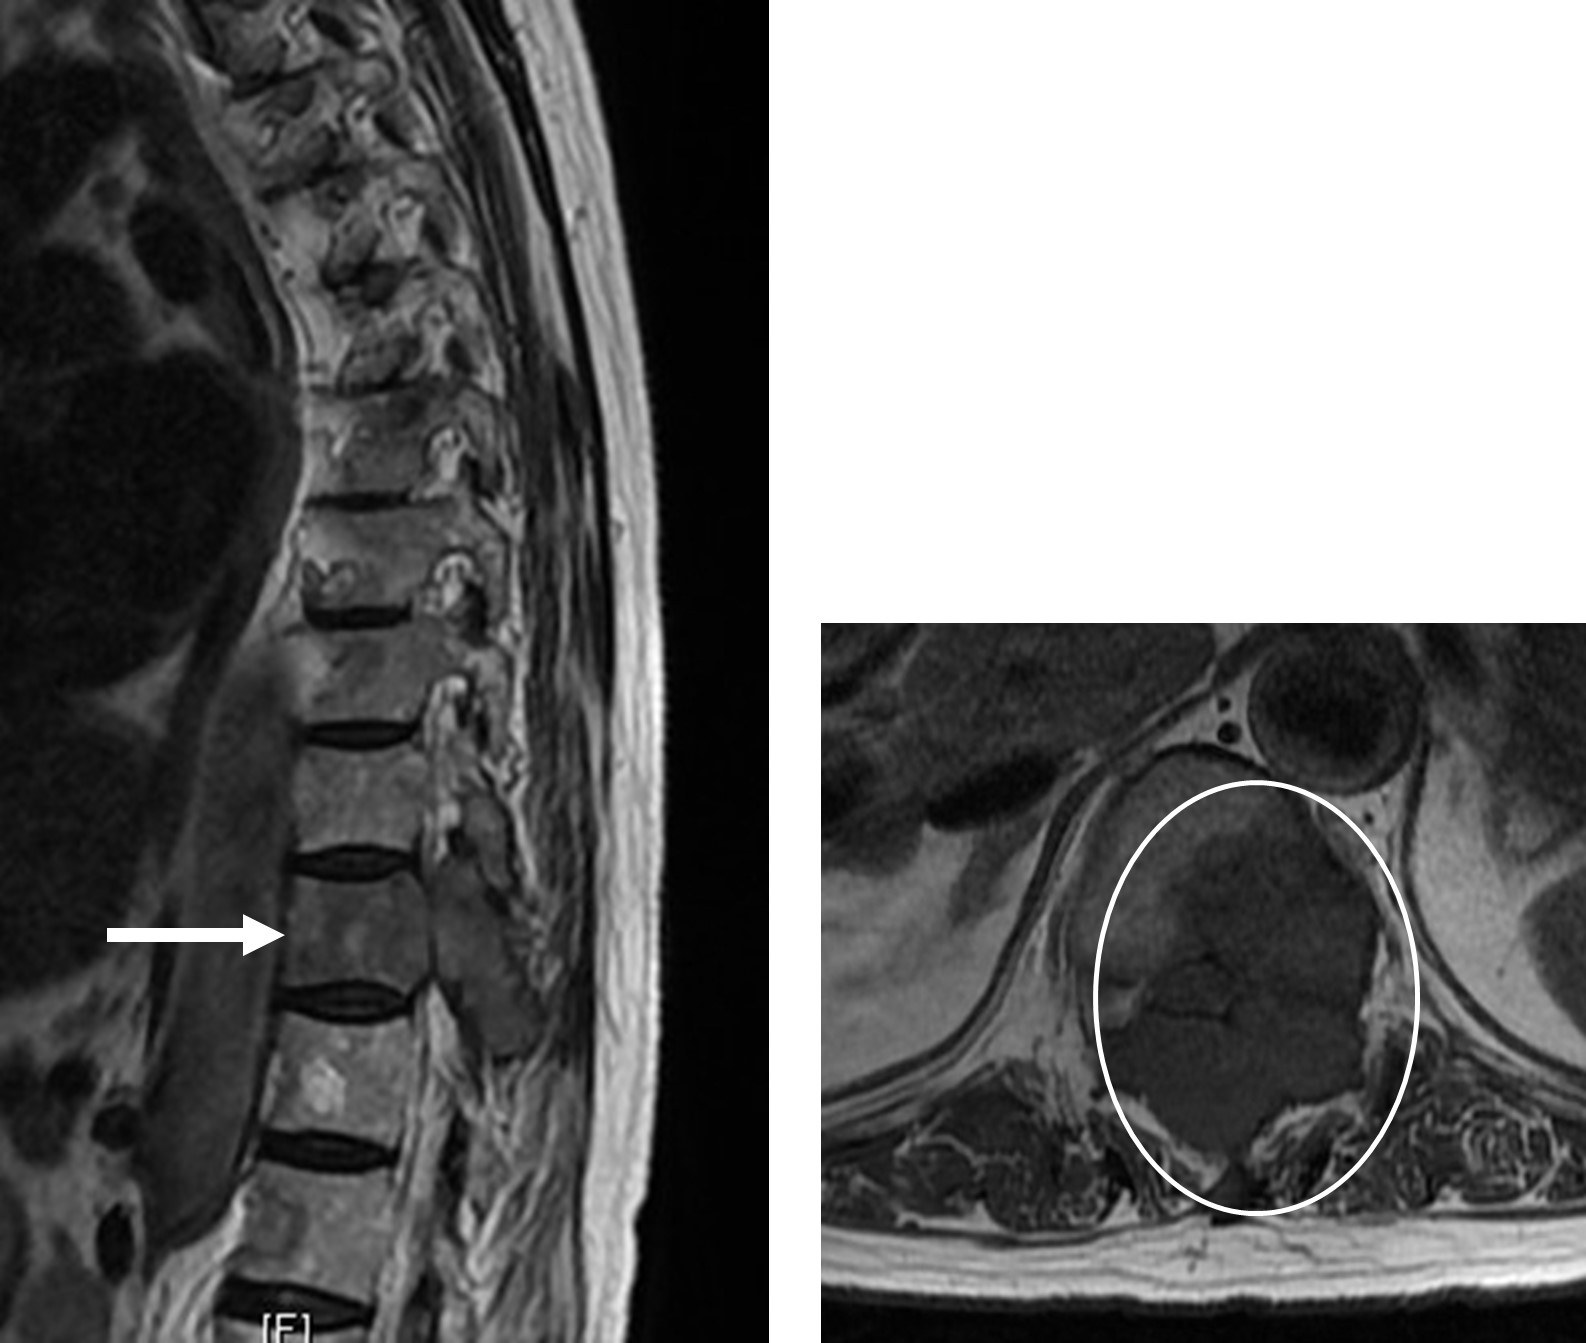

図 肺がんの転移性脊椎腫瘍 (矢印と〇で囲った黒い部分が腫瘍)